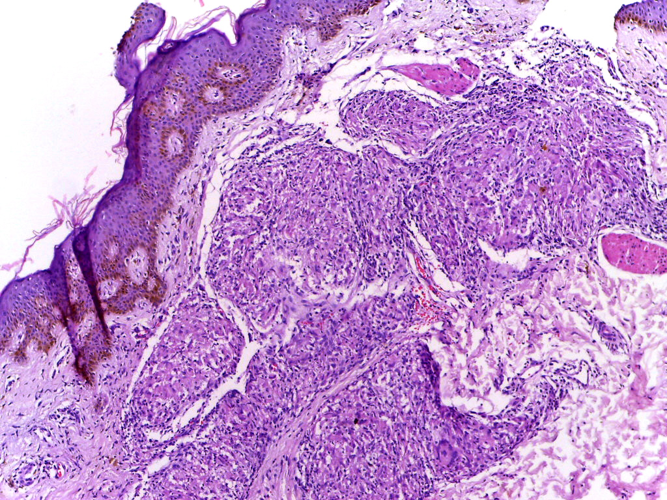

Section of skin showing epithelioid granulomas in the dermis and reduction in the number of appendages. (Department of Pathology, Calicut Medical College via Wikimedia Commons)

Leprosy leaves behind evidence of facial lesions and damage to the hands and feet caused by secondary infections, while TB affects the joints and bones near the lungs.